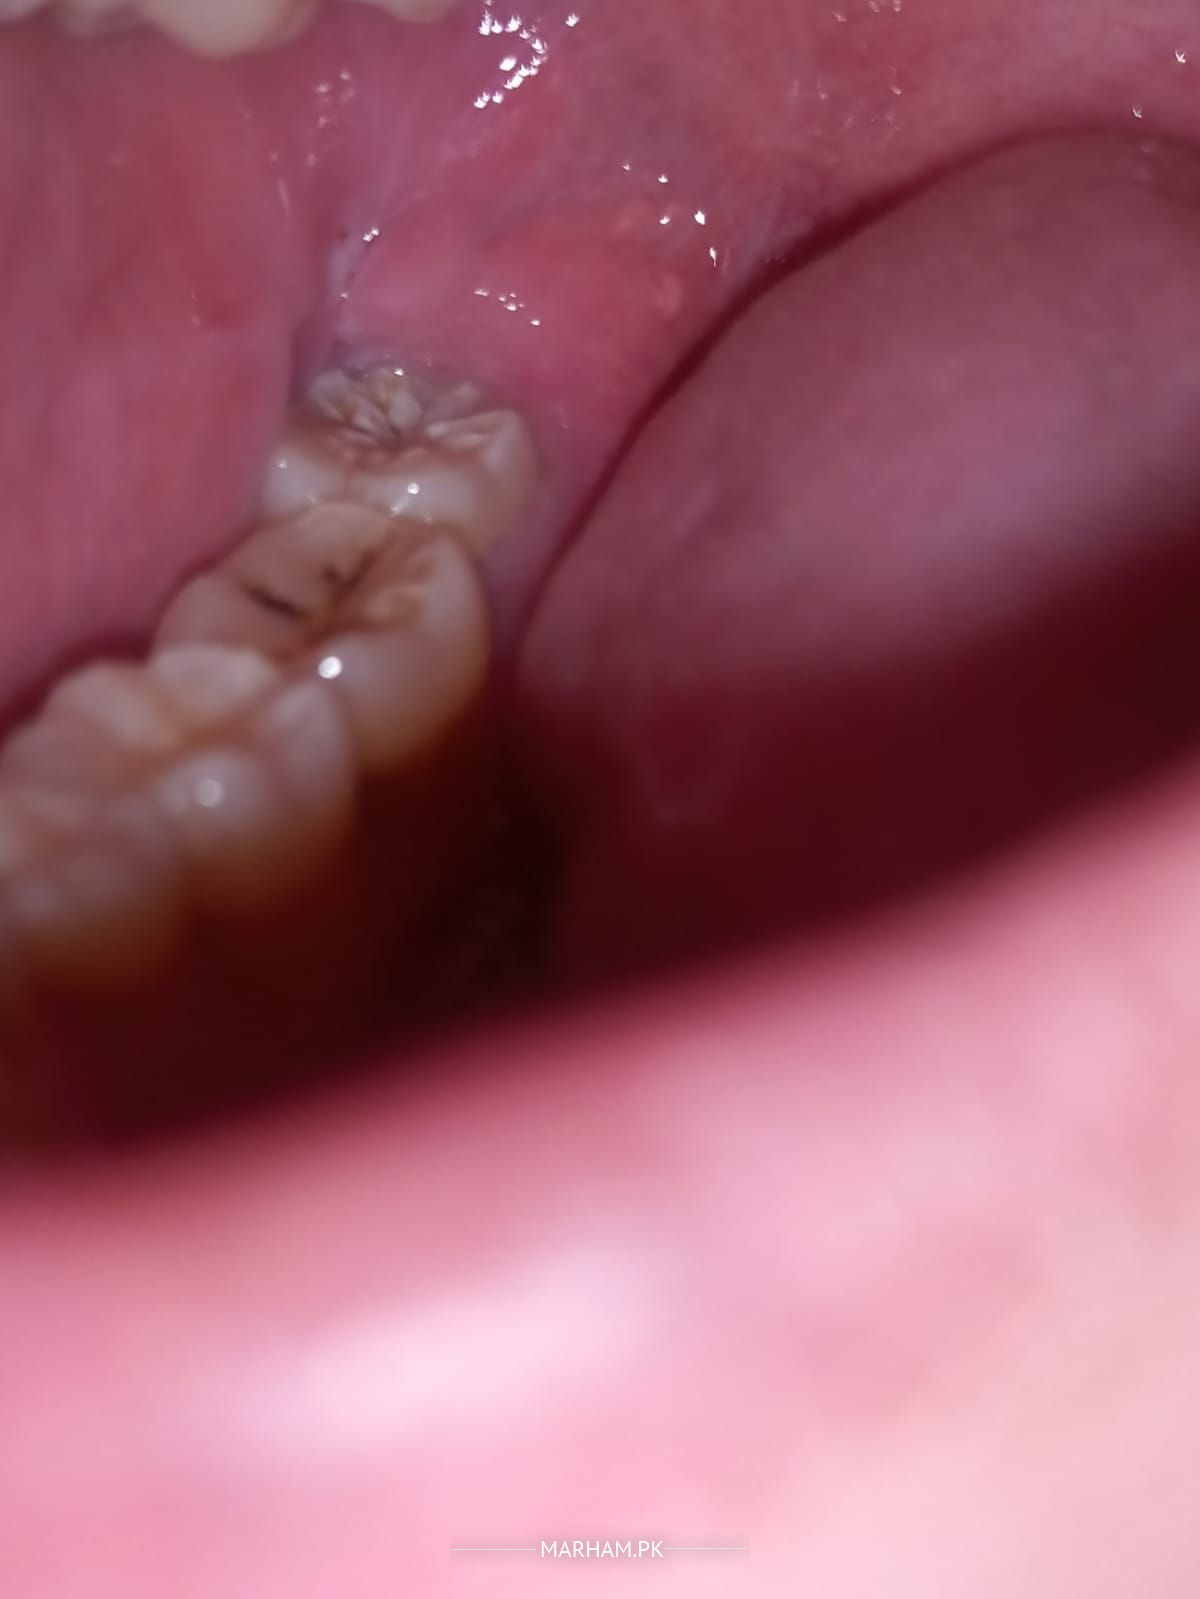

AslamWalaikum, Kal se mere End wale dant m dard ha Aur Ye achank se start hua ha. Please Advise

ap ki wisdom teeth ki waja se ye problem ho Rahe hai. go for scaling and take antibiotics us se behter ho jae ga.

but u need to remove this tooth if causing prob again

Wisdom tooth extraction hogi because it seems isky neeche infection hogai he

Doctor m Antibiotics le raha hn pain kafi km ha. Lekn gum pechy nhe hat rhi.

wisdom tooth seems to have infection as gum near to it is swollen and inflammmed.treatment fr that is extraction .take antibitiotic and for pain synflex 550mg.the tooth anterior to wisdom have also carious lesion so xray and evalaution is necessary.

Hey , you wisdom is erupting that is causing you a pin but need to evaluate the condition of the tooth #7 . For proper checkup kindly visit the clinic thankyou